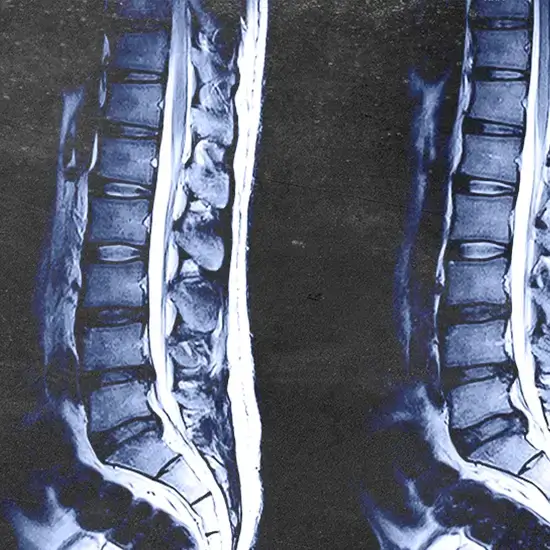

MRI screening of the lumbar is used to generate images of the lumbar spine with an MRI of the lower back (the bones, discs, spinal cord, and other structures in the lower back). This is used to diagnose any abnormality in the lumbar spine.

A lumbar spine MRI can find problems with the bones (vertebrae), soft tissues (like the spinal cord), nerves, and discs.